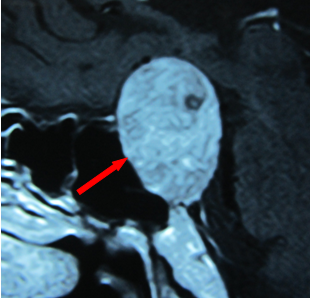

红箭头示垂体瘤

脑内垂体是人体内分泌激素最多的器官之一,其功能重要并复杂。近年来垂体瘤的发生率有上升趋势,并是第三位的脑内肿瘤(约占10%左右),但它属于良性肿瘤。其临床表现多种多样,主要取决于病理类型(8种类型)。其中的泌乳素细胞腺瘤(垂体腺瘤)最常见于青春期女性,临床表现有闭经、泌乳及不育等症状群,也是很多月经异常女性到处就医最后确诊的疾病之一。其他类型的垂体瘤也可能导致月经异常及不育。诊断垂体瘤必须具体以下三方面:临床症状、激素水平的异常及垂体影像学上的异常。治疗上有手术、药物及放射性治疗的三种方案。大多数垂体瘤的预后良好,特别是对生理性月经的恢复明显有效。